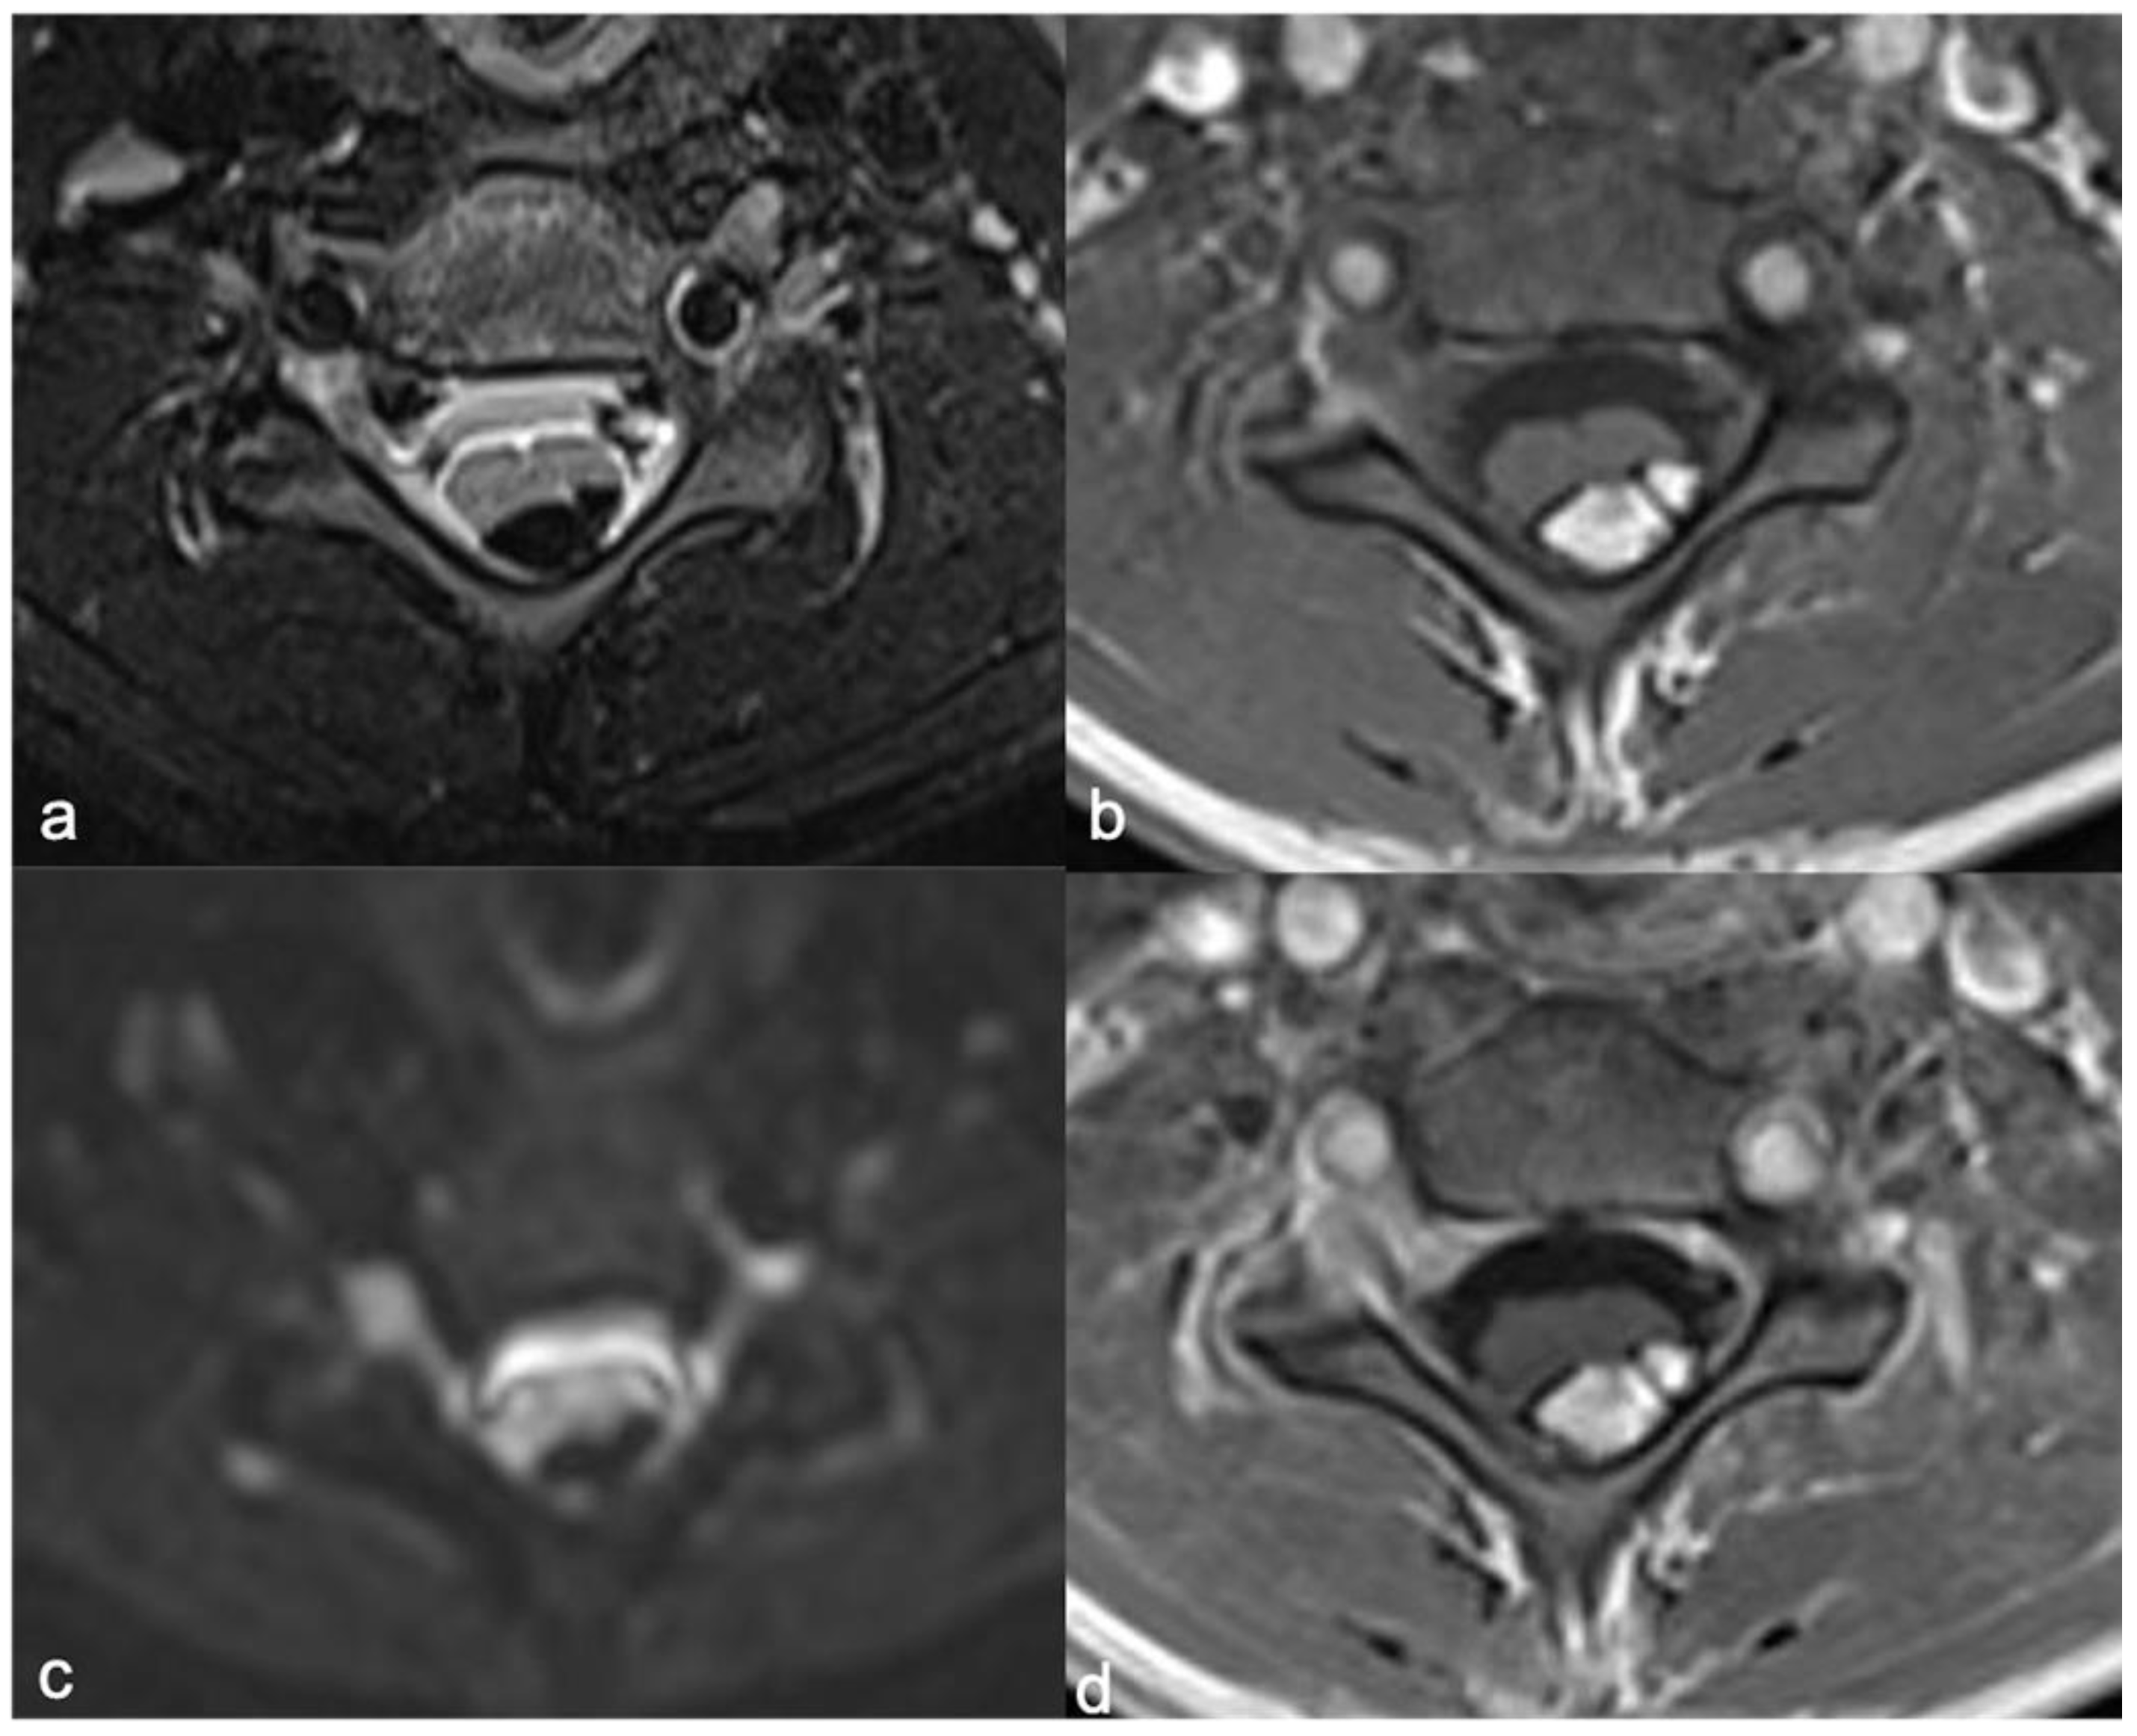

Currently, MRI protocol includes a standard pre-contrast study, such as sagittal (and axial) T1 and T2 sequences (thickness: 3 mm) and axial, sagittal (and coronal) T1 sequences after contrast [89]. In addition, heavily T2-weighted MR “cisternography” sequences (e.g., CISS, “constructive interference in steady-state” and DRIVE, “3D driven equilibrium”), fat suppression sequences (T1- or T2-weighted), diffusion-weighted imaging (DWI), 3D volumetric sequences, and susceptibility-weighted imaging (SWI) can be used. The 3D-CISS sequence, characterized by a high spatial resolution, allows a detailed view (Figure 13 and Figure 14) of small components (for example spinal roots, cysts) with three-plane visualization (isotropic sequence) [90]. SWI, related to the magnetic susceptibility of the different tissue components, has a recognized role in the brain but its role is limited and not standardized in the spinal cord [90]. In the brain, it is used to detect bleeding, calcifications, iron, and deoxygenated hemoglobin; in the spine, its potential uses include the evaluation of venous anatomy [91] and, therefore, the results of vascular malformation treatments [92] and bleeding (potential use in ependymoma). Advanced neuroimaging methods, such as diffusion-weighted imaging (DWI), can be useful techniques, mostly to increase conspicuity in the detection of spinal metastases. The DWI technique is based on the motion of extracellular water molecules—the increase in the number of cells (neoplasms with high cellularity) causes a reduction in the movement of extracellular water (decreased diffusion of extracellular water; high cellularity = diffusion restricted) [93].

Figure 13.

Leptomeningeal dissemination related to medulloblastoma. CISS (a), post-contrast T1-weighted (b) and T2-weighted (c) images show diffuse nodular appearance of the meningeal sheets (arrowheads). The panel demonstrates more detail of the CISS (a) than the T2-weighted image (c).

Figure 14.

Another case of leptomeningeal dissemination related to medulloblastoma, in which the usefulness of the CISS (a) is clear compared to post-contrast T1-weighted (b) and T2-weighted (c) images. Nodular appearance of the cauda roots is evident (arrowheads).